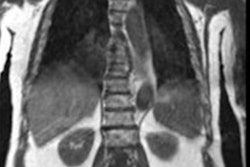

Whole-body MRI with diffusion-weighted imaging (DWI) is a viable alternative to F-18 FDG-PET/CT imaging for lung cancer staging, according to research presented at the recent ECR meeting in Vienna.

"Whole-body MRI is an ideal radiation-free imaging tool for the staging of lung cancer with good diagnostic accuracy," said presenter Dr. Ajith Antony of All India Institute of Medical Sciences (AIIMS) in New Delhi, India.

Whole-body MRI shows promise as an attractive alternative for lung cancer staging because it does not impart radiation, but there have been few studies evaluating its performance for this indication, Antony said. To compare the two exams, he and colleagues conducted a study that included 31 patients with biopsy-proven lung cancer.